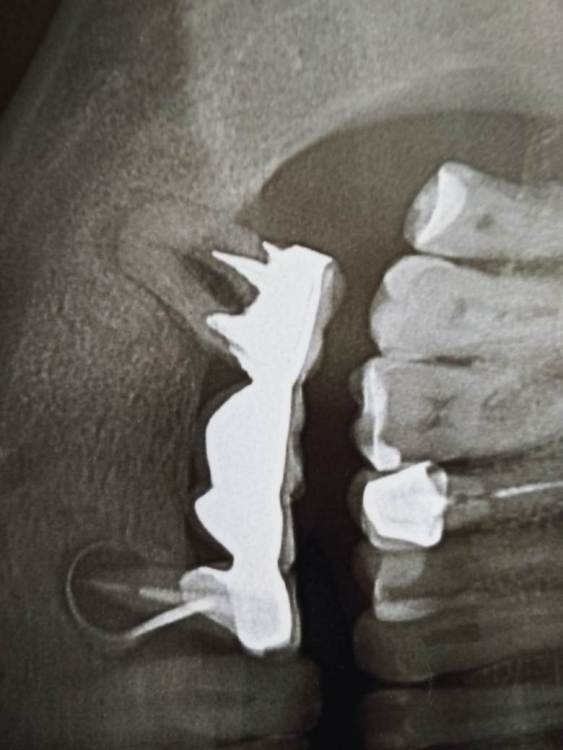

Александр Ле Опубликовано 8 августа, 2023 Поделиться Опубликовано 8 августа, 2023 На десне , под зубом на котором закреплен мост - свищ. Есть ли возможность снять мост, вылечить зуб и поставить мост обратно? В Ярославле это делают? Ссылка на комментарий

kuziy12 Опубликовано 9 августа, 2023 Поделиться Опубликовано 9 августа, 2023 Доброго времени суток. Мост нужно снимать. Зубы, которые под мостом - процентов 99, что удалять. 4.7 из- за пародонтальных проблем(грубо говоря - проблема с костью и десной), зуб 4.5 из за очага воспаления на верхушки корня. 1 Ссылка на комментарий

Doc Опубликовано 9 августа, 2023 Поделиться Опубликовано 9 августа, 2023 В данном случае шансов нет даже теоретических. Увы. Удалять и имплантацию делать, либо съемный протез. 1 Ссылка на комментарий

kuziy12 Опубликовано 9 августа, 2023 Поделиться Опубликовано 9 августа, 2023 11 минут назад, Александр Ле сказал: Спасибо. А костной ткани достаточно для имплантации? А что будет, если все оставить как есть? Для оценки костной ткани нужно делать КТ. Здесь, скорее всего, разумным вариантом будет удаление зубов, подождать полного заживления(2-3 месяца) и только потом обращаться на консультацию к имплантологу. Бездействие может привести к печальным последствиям - на зубе 4.5 инфекции будет развиваться и когда-нибудь случиться периостит(флюс в простонародье или отек). Я предполагаю, что у вас уже есть неприятный запах из полости рта. Скоро появится подвижность зубов и моста(если уже ее нет). Ссылка на комментарий